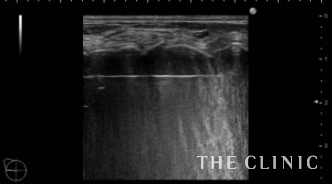

脂肪が崩れた後は吸引を行い、しこりは消失しました。右側は吸引除去した壊死脂肪です。